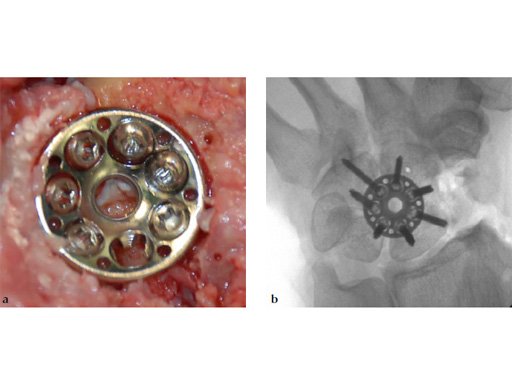

Fig 6ab Final appearance of fixed plate.

The 2.4 mm VA-locking intercarpal fusion system combines a circular plating technique with 2.4 mm variable angle locking technology and dedicated instrumentation . The circular plate design with a smooth surface and rounded edges minimizes soft-tissue irritation (Fig 2). To avoid impingement, proper positioning of the fusion as well as accurate placement and recession of the implant is mandatory. In addition to the standard reaming guide (Fig 3 in Instrument tab), the new reduction reaming guide permits reduction, compression and stabilization of the fusion site during the reaming procedure (Fig 4 in Instrument tab). Laser markings on the reamer support the surgeon by precisely controlling the depth of reaming for optimal countersinking of the plate (Fig 5 in Instrument tab).

The available two plate sizes include a 6-hole plate with a diameter of 15 mm, and a 7-hole plate with a diameter of 17 mm to fit different sized patients and applications.